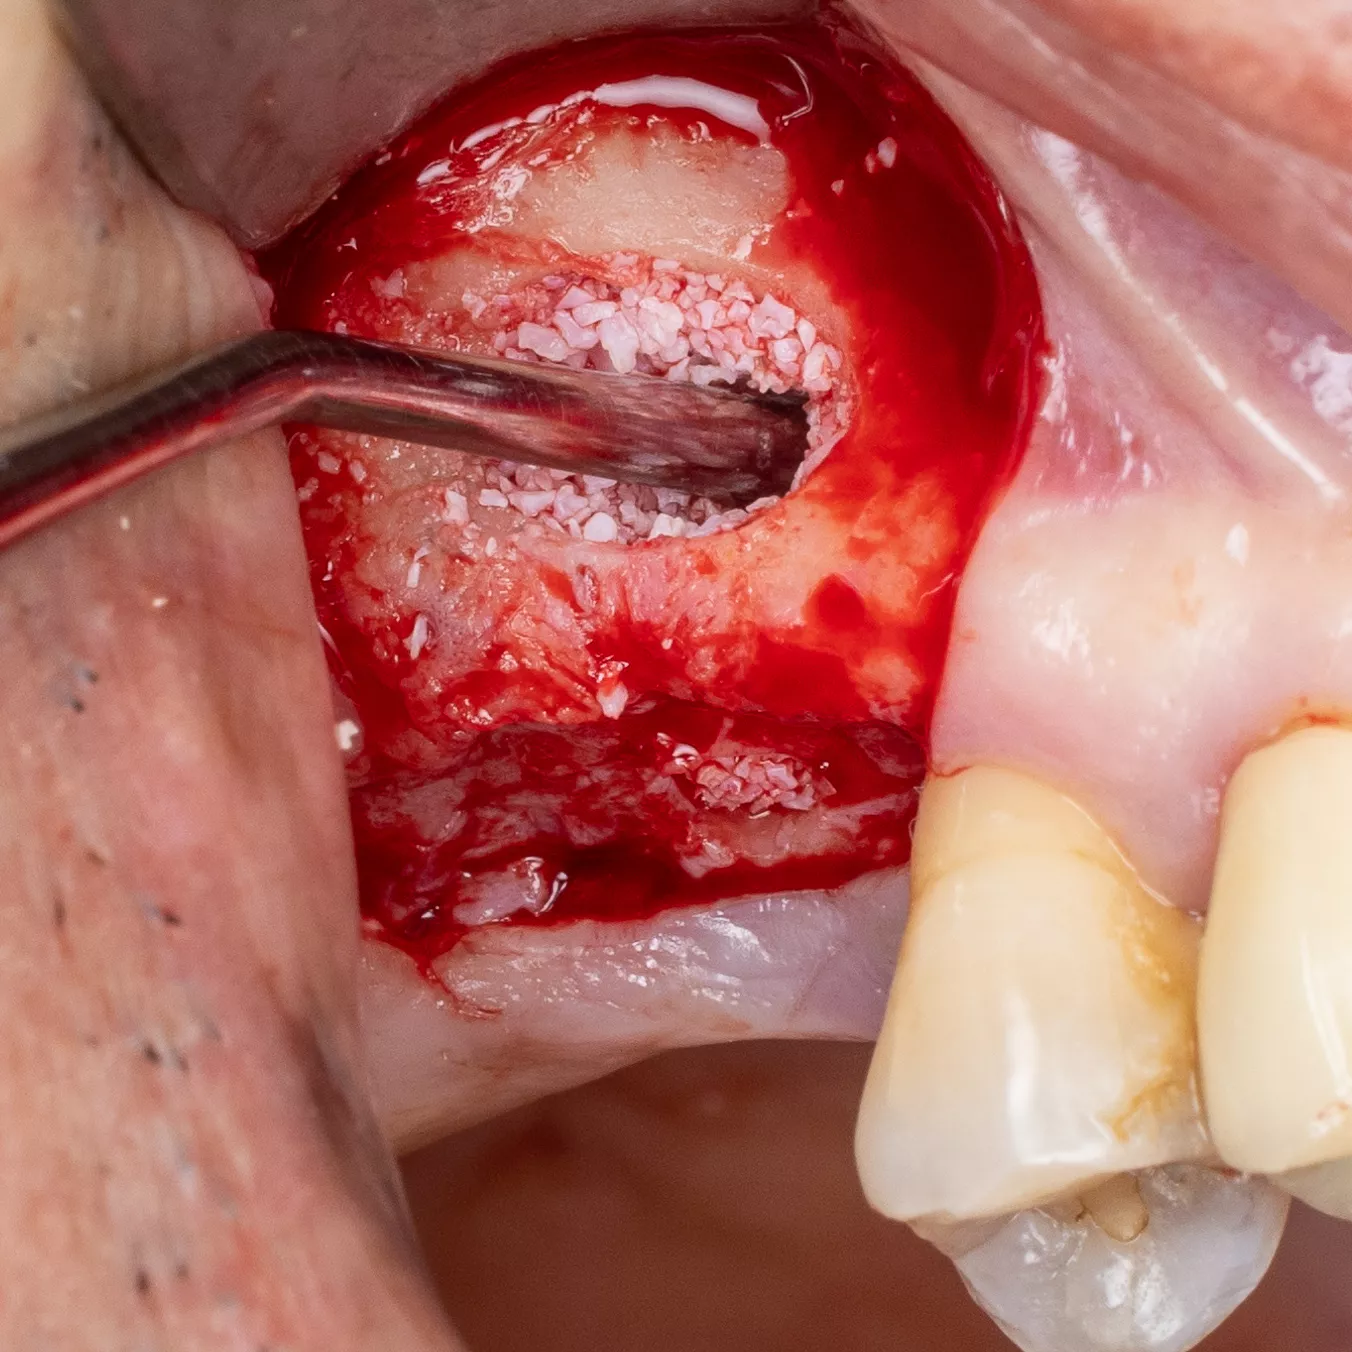

16. Prior to implant placement, filling of the palatal and mesial area of the sinus cavity with axenogenic biomaterial (XenoGraft, Straumann®).

17. Filling and compression using a graft packer in the mesio-palatal direction.

18. The sinus cavity is densely packed with the bone graft composite to support the implant.